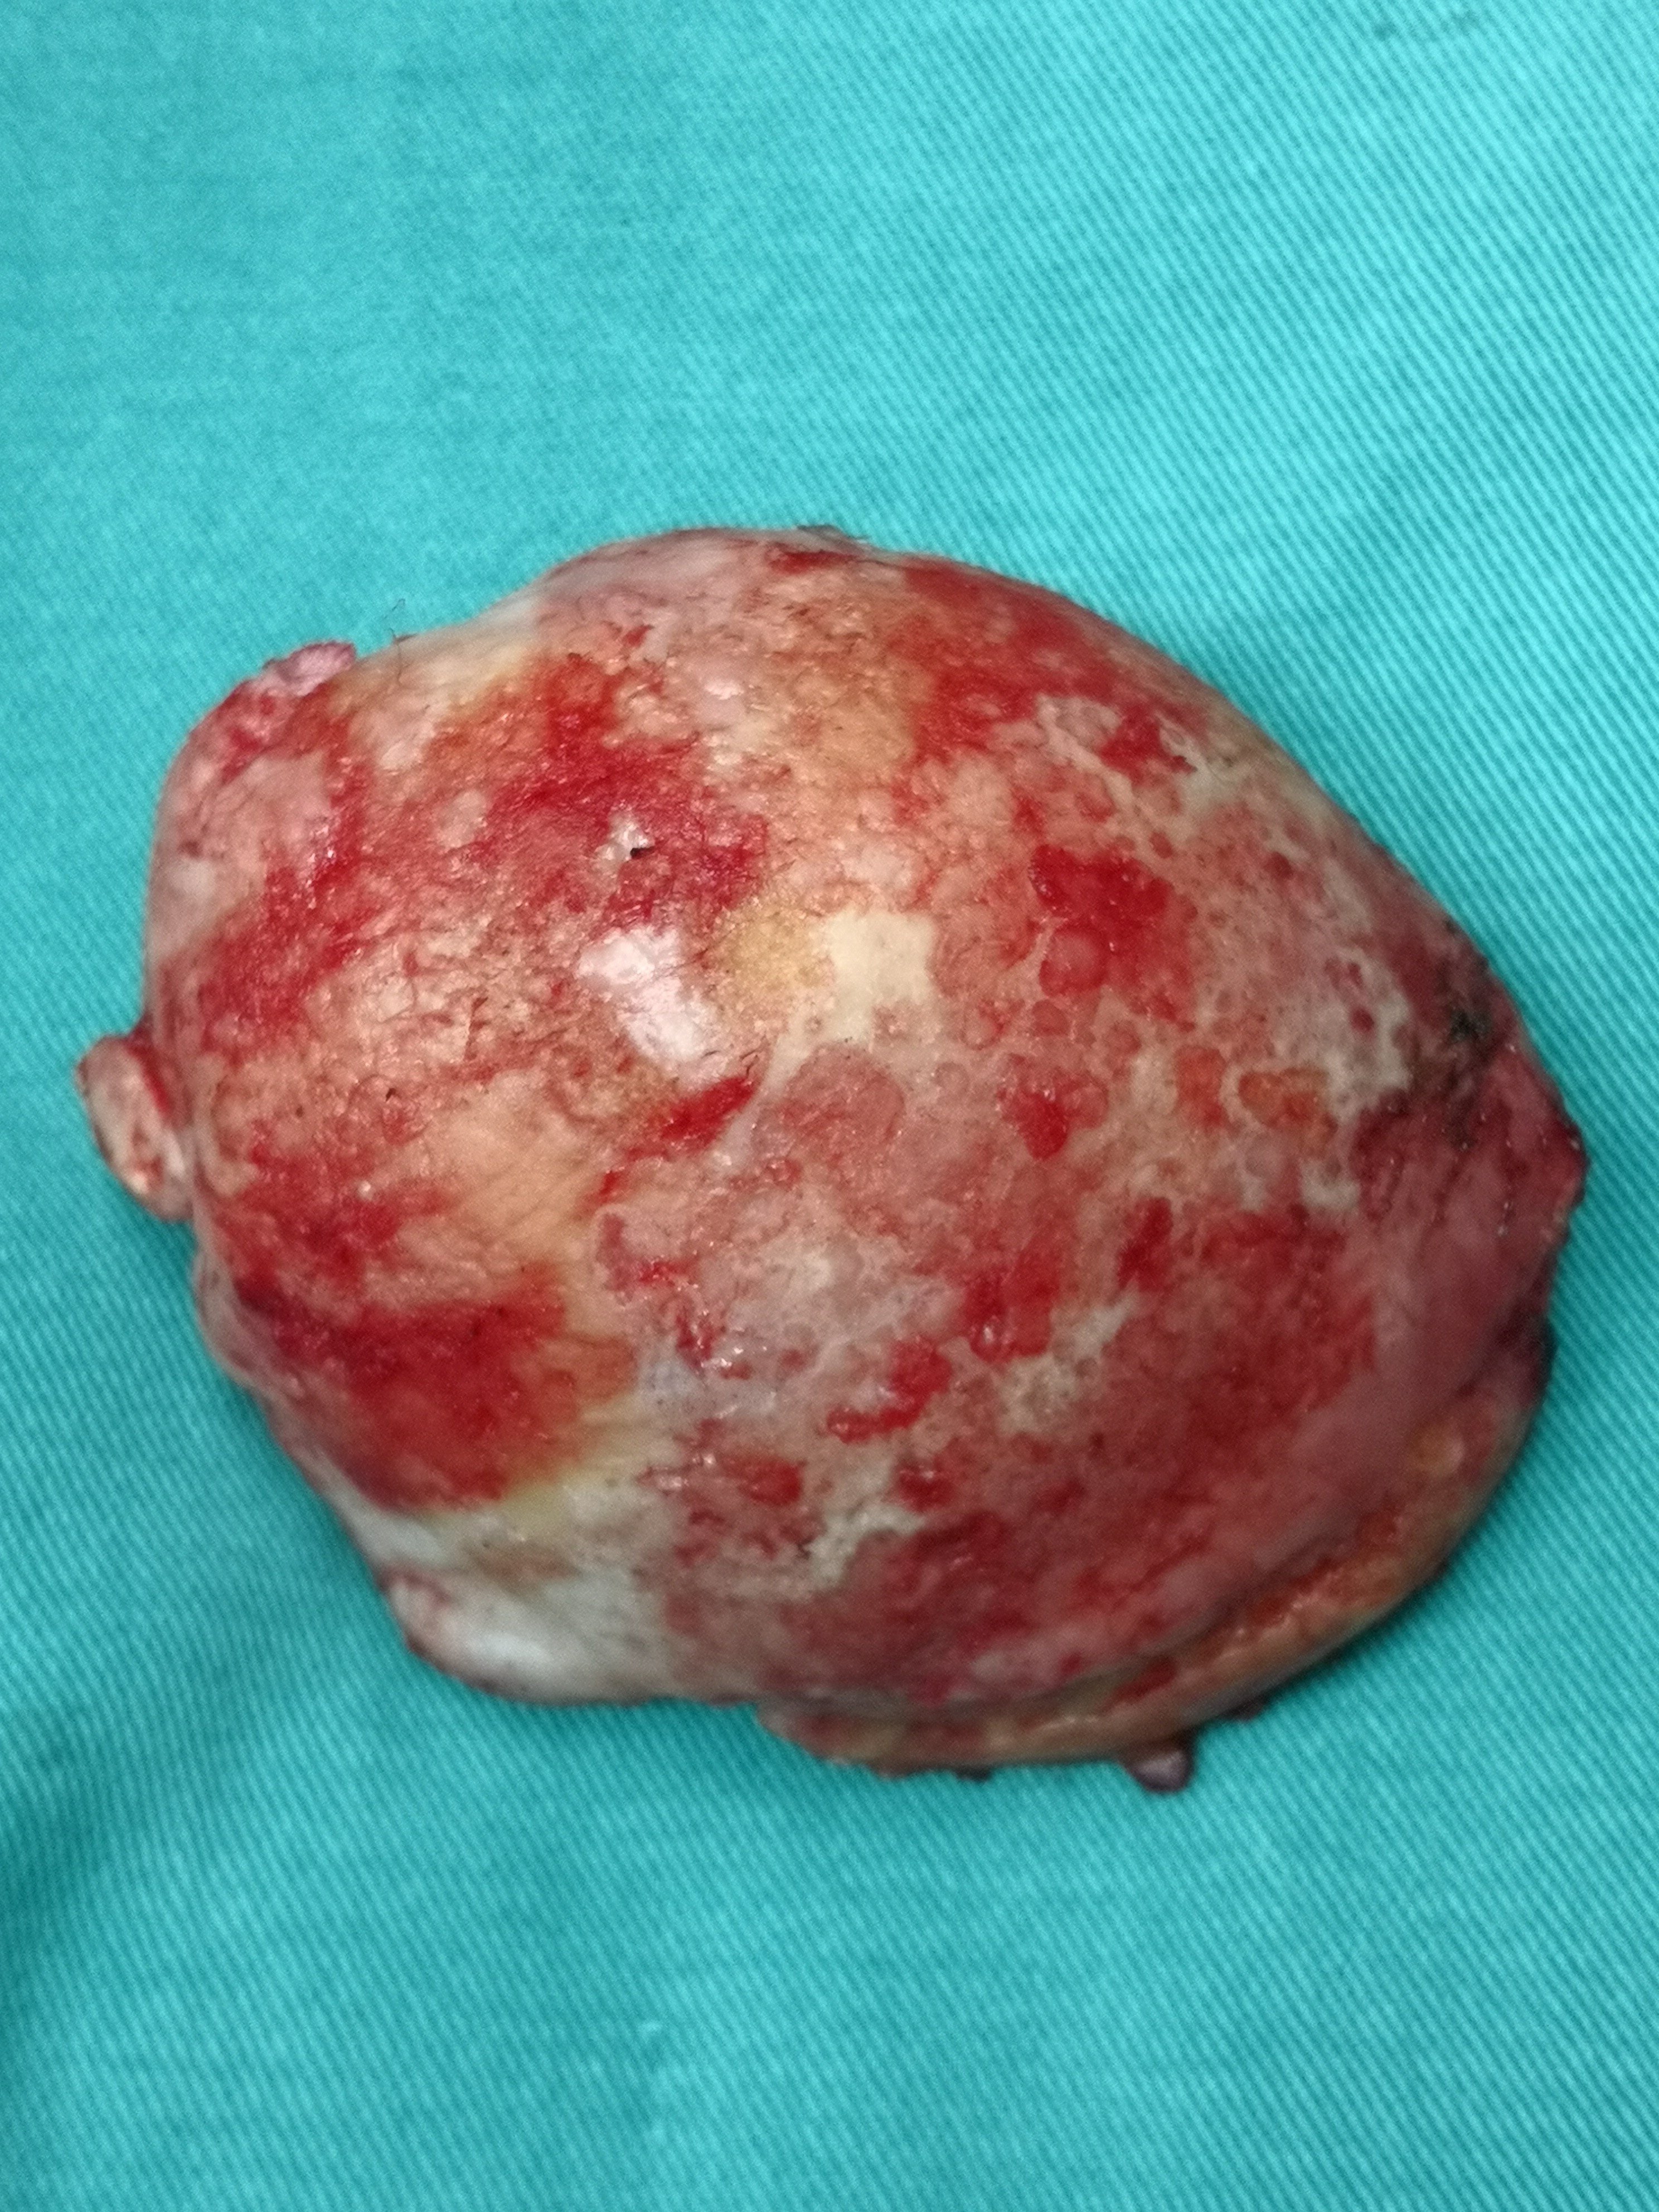

患者60岁,抽烟(每天2包)及外伤导致双侧股骨头坏死30余年。但一直未做治疗,近期疼痛加重,行走跛行,双下肢不等长,双髋关节外展受限。住院后给予双侧腹股沟区内收肌松解术,并行双侧全髋关节置换术。术中见髋臼严重增生,股骨头变形呈蘑菇状,股骨近端硬化,髓腔消失,被硬化骨全覆盖。髋臼侧卵圆窝消失,被增生骨覆盖。髋臼边缘增生明显。去除大量增生骨,给予再造髋臼及股骨近端成型术,顺利完成双侧髋关节置换手术。术后病人恢复良好。术后三天可以去除助行器自己行走。